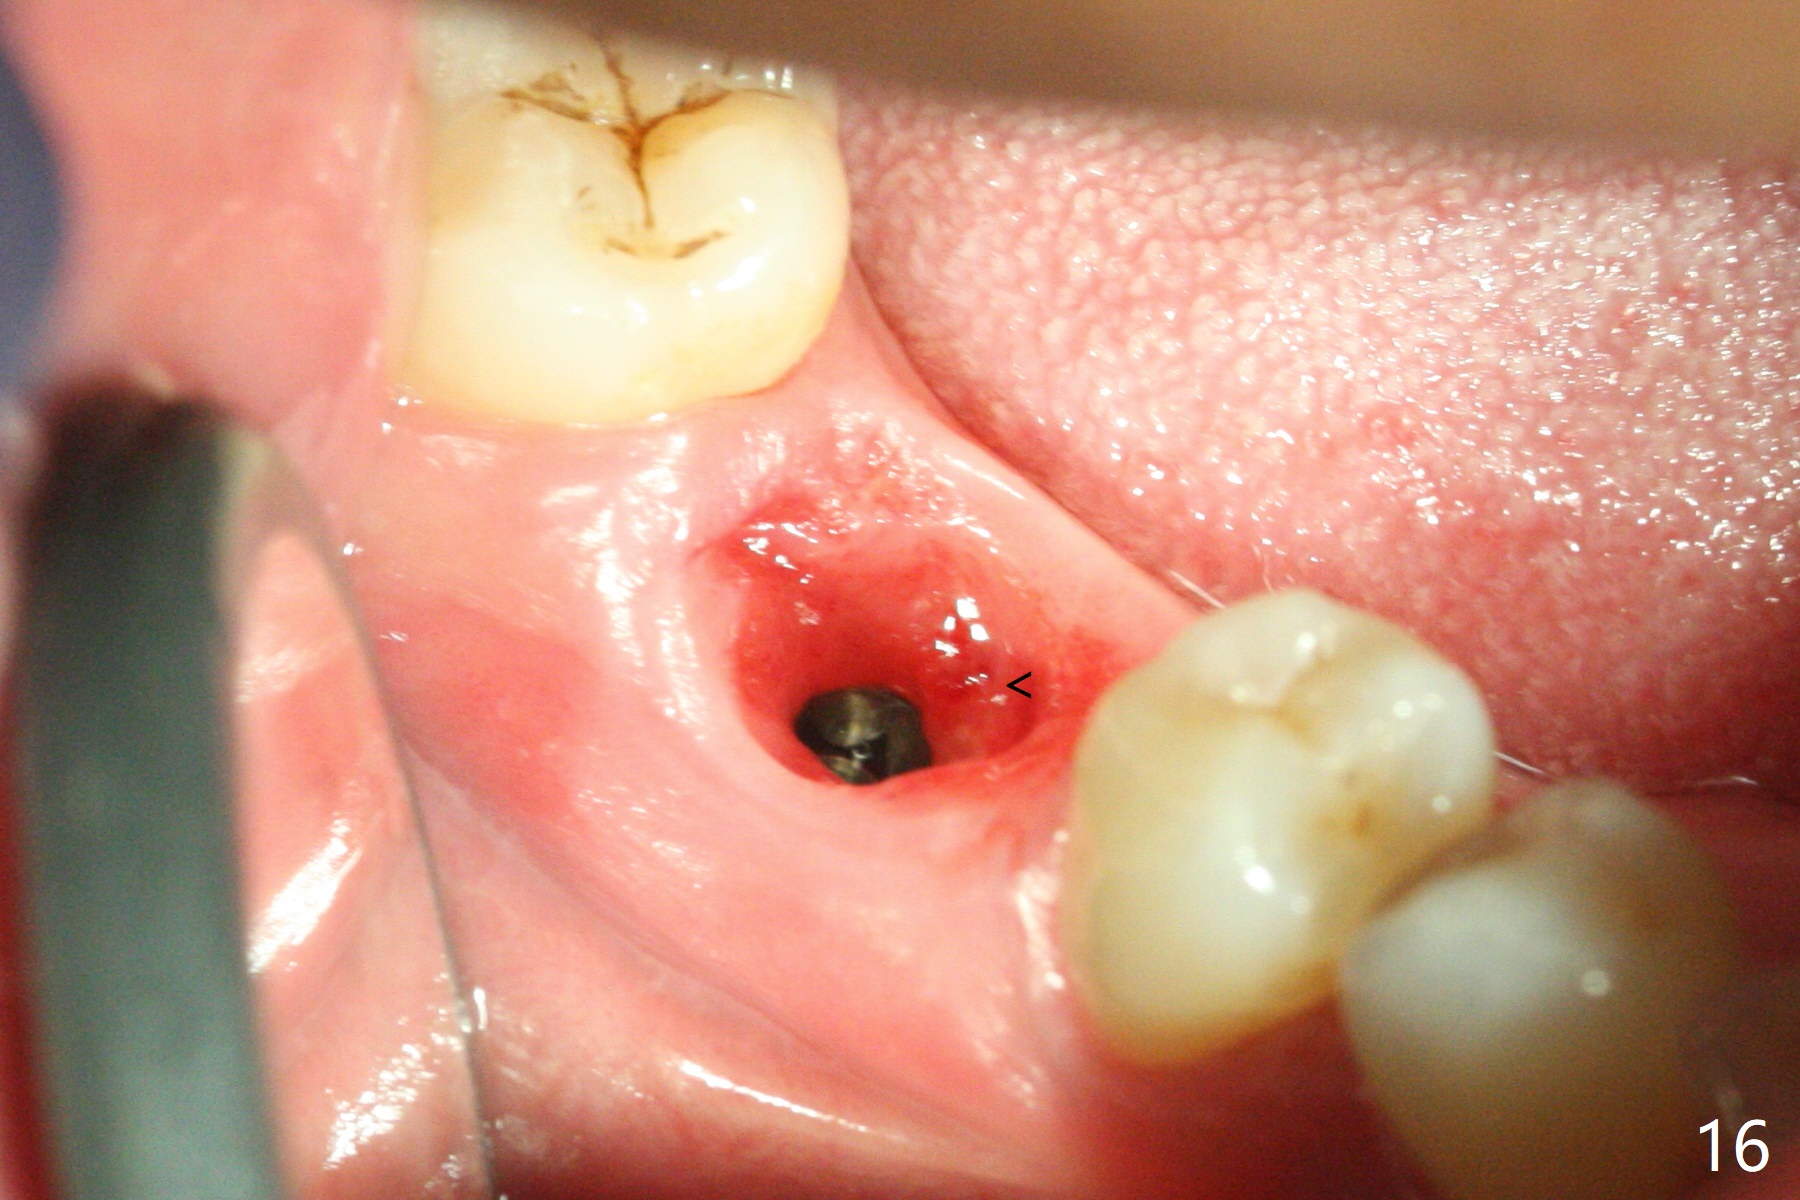

Fortunately no paresthesia is reported postop. Why is the Inferior Alveolar Canal not violated? Fig.7 is a coronal section of CBCT taken for a 40-year-old man at the lower 1st molar (at the septum). At the region, the Canal (brown circle) is close to the lingual plate (L). Because of severe bone loss of the lingual plate of this case (Fig.8 *), osteotomy is intentionally created buccal (green). The deep osteotomy may not contact the Canal, while the hemorrhage may stem from the medullary space (M in Fig.4,7). Bone morphology at the coronal end of the implant apparently changes 4 months postop, suggesting osteointegration (Fig.9). Impression is taken. Bone density around the implant at the crest seems to increase (Fig.10), while there is no soft tissue deficiency 10 months post cementation (Fig.11). The bone appears to regenerate toward the abutment, particularly distally, 14.5 months post cementation (Fig.12). Periimplantitis develops (bleeding on water pik and erythematous and tender buccal gingiva) 1 year 7 months post cementation (Fig.13,14). The 1st three threads are exposed (*). Bone graft with PRF and 6-month membrane or Cytoplast will be needed. Pain disappears 3 days of oral antibiotic. The gingiva looks healthy 1 month later when he returns for bone graft (Fig.15). But the lingual gingival cuff is not so healthy when the crown/abutment is removed (Fig.16 <). Bone graft is not done. For those patients with suboptimal oral hygiene, implants should be placed as low as possible, better with guide for precision.